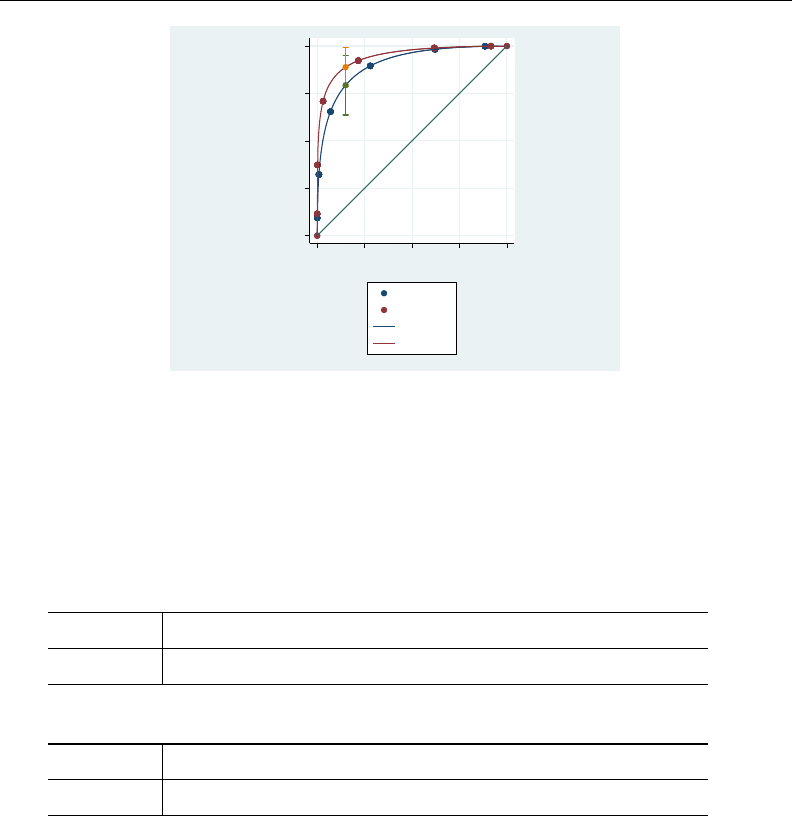

- roc

- roccomp

- rocfit

- rocfit postestimation

- rocreg

- rocreg postestimation

- rocregplot

- roctab